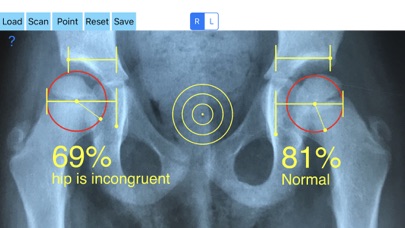

Treatment of incongruity is paramount importance because you have to address it early and the treatment of choice are usually corrective hip osteotomies. In order-from one hand to avert the natural course to the progression of secondary osteoarthritis (OA) and from another hand to avoid- in developing skeleton - to deteriorate more the hip dysplasia the congruity must be objectively and thoroughly evaluated especially at follow up of these procedures in both congruent and incongruent hips. Congruity between the femoral head and acetabulum is determined by the percentage of femoral head covered by the bony acetabulum. The congruity index (CI) is calculated (A/B- ratio converted to a percentage) by diving the (A) distance by the distance (B), where distance (A) is the distance between the teardrop to the lateral acetabular margin and (B) is the distance from the teardrop again to the lateral femoral head edge.

-Offers a very convenient way to determine the most accurate possibly way an objective value of congruity. By clicking three point at the x-ray picture on your iPhone screen and inserting the side the App calculates the congruity index (CI) which is the percentage of femoral head covered by the bony acetabulum. Congruity between the femoral head and acetabulum is expressed in percentage. Values of Coverage less than 75% is considered pathologic in another words the hip is incongruent